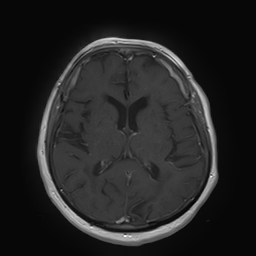

(a) Guide 𝑮𝑮\boldsymbol{G}

Refer to caption

(b) Input 𝑰𝑰\boldsymbol{I}

(c) Guidance map 𝑴𝑴\boldsymbol{M}

(d) Prediction 𝑷𝑷\boldsymbol{P}

(e) Ground truth

(f) Guide 𝑮𝑮\boldsymbol{G}

(g) Input 𝑰𝑰\boldsymbol{I}

(h) Guidance map 𝑴𝑴\boldsymbol{M}

(i) Prediction 𝑷𝑷\boldsymbol{P}

(j) Ground truth

Figure 2: Inputs and outputs of the guided filtering pipeline based on the WDSR network. T1 & T2 MRI pairs (a)-(e) and CT & MRI projection images (f)-(j).

In Fig. 2 and 4, exemplary input, output and label images of the pipeline are presented for both tasks. Additional super-resolved images for both network architectures with and without the guided filter can be seen in Fig. 3. The results show a consistently high quality over both, the tomographic and the projective domain, as well as both tasks. Corresponding quantitative evaluation can be found in Table I and II. For SR, the WDSR network, i.e., the designated super resolution network, performs consistently better for both datasets with and without the guided filter. Applied to the tomographic images, the approaches without the guided filter deliver slightly better quantitative results. For the projection images this difference diminishes and both approaches are on par. In the case of denoising, the approaches with the guided filter deliver a lower mean absolute error while the structural similarity is increased without it. Though, the measurable differences are only marginal. The results generated by the plain guided filter without the learned guidance map are numerically worse than the approaches empowered by the guidance map generator for all tasks. This observation is most prevalent when observing the results of the tomographic T1 and T2 Flair images for SR, while for denoising the results are closer to the deep learning-based approaches.